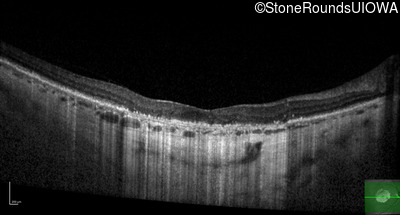

Optical Coherence Tomography - Right - 10/300

Exemplar / OCT Stack